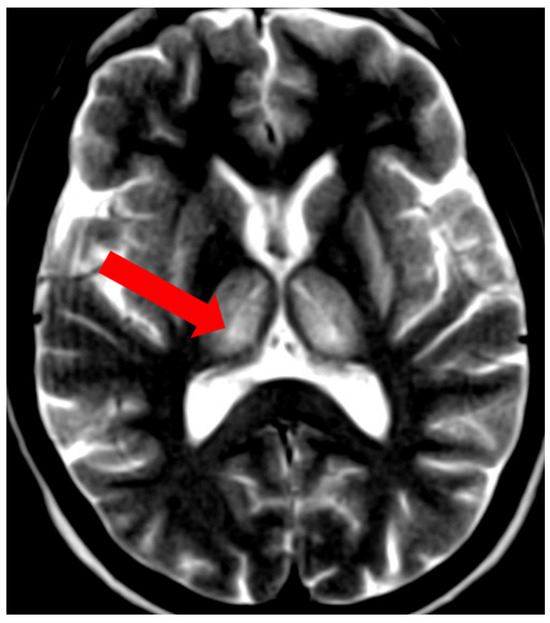

- Rędzia-Ogrodnik, B.; Członkowska, A.; Antos, A.; Bembenek, J.; Kurkowska-Jastrzębska, I.; Przybyłkowski, A.; Skowrońska, M.; Smoliński, Ł.; Litwin, T. Pathognomonic neuroradiological signs in Wilson’s disease—Truth or myth? Park. Relat. Disord. 2023, 107, 105247. [Google Scholar] [CrossRef] [PubMed]

- Hitoshi, S.; Iwata, M.; Yoshikawa, K. Mid-brain pathology of Wilson’s disease: MRI analysis of three cases. J. Neurol. Neurosurg. Psychiatry 1991, 54, 624–626. [Google Scholar] [CrossRef] [PubMed]

- George, U.; Varte, N.; Rathore, S.; Jain, V.; Goyal, S. “Split thalamus”: Internal medullary involvement in Wilson’s disease. Neurol. India 2010, 58, 680. [Google Scholar] [CrossRef] [PubMed]

- Sener, R.N. The claustrum on MRI: Normal anatomy, and the bright claustrum as a new sign in Wilson’s disease. Pediatr. Radiol. 1993, 23, 594–596. [Google Scholar] [CrossRef] [PubMed]

- Prashanth, L.K.; Sinha, S.; Taly, A.B.; Vasudev, M.K. Do MRI features distinguish Wilson’s disease from other early onset extrapyramidal disorders? An analysis of 100 cases. Mov. Disord. 2010, 25, 672–678. [Google Scholar] [CrossRef] [PubMed]

- Vella, S.; Grech, R. Highlighting an atypical cause of the Face of the Giant Panda sign. BJR Case Rep. 2018, 4, 20170046. [Google Scholar] [CrossRef] [PubMed]